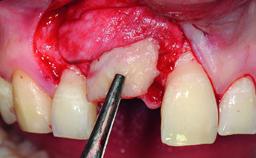

A 15-year-old male patient was referred to us by his pediatric dentist in June 2004 for evaluation of treatment options for his failing tooth 21. The patient had recently seen an endodontist for internal bleaching and been advised that there had been significant resorption and ankylosis. The patient’s mother was concerned because the tooth appeared shorter than the adjacent one. His past dental history was significant for trauma (September 2001), where the tooth had been avulsed and reimplanted. Teeth 11 and 21 had been endodontically treated.

| Bone Augmentation | Horizontal|Simultaneous|Staged |

| Augmentation Materials | Autogenous chips|Xenogenous |